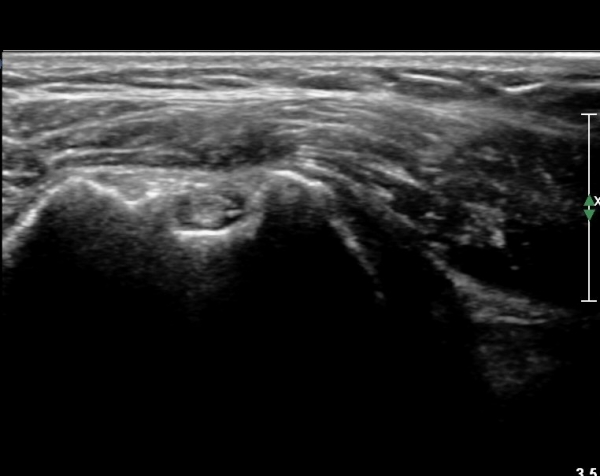

ŽÃËÀÚ¸¦ Á¶±Ý ¾Æ·¡·Î À̵¿ÇÏ¿© À̵ιڱٰÇÀÇ È¾´Ü¸é°Ë»ç¿¡¼­ ÀÌµÎ¹Ú±Ù°Ç ÁÖÀ§ ¼ö¾×Àú·ù°¡ °üÂûµÈ´Ù(»çÁø 3, 4).

À̴ Ȱ¾×¸·¿°Áõ ¼Ò°ßÀ¸·Î Ãæµ¹ÁõÈıº ¶Ç´Â ȸÀü±Ù°³ ÆÄ¿­ ½Ã ÈçÈ÷ °üÂûµÇ´Â

¼Ò°ßÀÌ´Ù.